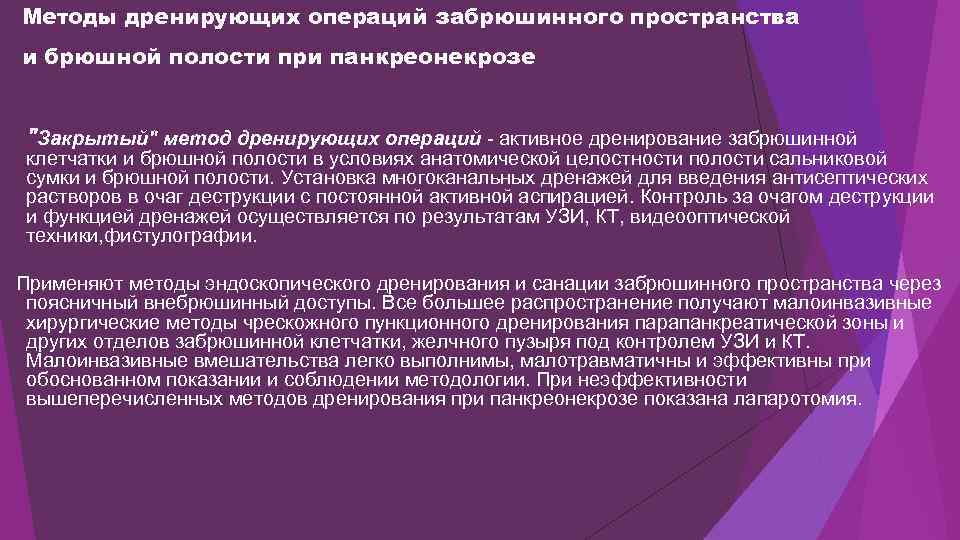

Методы дренирующих операций забрюшинного пространства и брюшной полости при панкреонекрозе "Закрытый" метод дренирующих операций - активное дренирование забрюшинной клетчатки и брюшной полости в условиях анатомической целостности полости сальниковой сумки и брюшной полости. Установка многоканальных дренажей для введения антисептических растворов в очаг деструкции с постоянной активной аспирацией. Контроль за очагом деструкции и функцией дренажей осуществляется по результатам УЗИ, КТ, видеооптической техники, фистулографии. Применяют методы эндоскопического дренирования и санации забрюшинного пространства через поясничный внебрюшинный доступы. Все большее распространение получают малоинвазивные хирургические методы чрескожного пункционного дренирования парапанкреатической зоны и других отделов забрюшинной клетчатки, желчного пузыря под контролем УЗИ и КТ. Малоинвазивные вмешательства легко выполнимы, малотравматичны и эффективны при обоснованном показании и соблюдении методологии. При неэффективности вышеперечисленных методов дренирования при панкреонекрозе показана лапаротомия.

Методы дренирующих операций забрюшинного пространства и брюшной полости при панкреонекрозе "Закрытый" метод дренирующих операций - активное дренирование забрюшинной клетчатки и брюшной полости в условиях анатомической целостности полости сальниковой сумки и брюшной полости. Установка многоканальных дренажей для введения антисептических растворов в очаг деструкции с постоянной активной аспирацией. Контроль за очагом деструкции и функцией дренажей осуществляется по результатам УЗИ, КТ, видеооптической техники, фистулографии. Применяют методы эндоскопического дренирования и санации забрюшинного пространства через поясничный внебрюшинный доступы. Все большее распространение получают малоинвазивные хирургические методы чрескожного пункционного дренирования парапанкреатической зоны и других отделов забрюшинной клетчатки, желчного пузыря под контролем УЗИ и КТ. Малоинвазивные вмешательства легко выполнимы, малотравматичны и эффективны при обоснованном показании и соблюдении методологии. При неэффективности вышеперечисленных методов дренирования при панкреонекрозе показана лапаротомия.

Открытый метод дренирующих операций Основными показаниями к "открытому" методу дренирования забрюшинного пространства являются: - крупномасштабные формы панкреонекроза в сочетании с поражением забрюшинной клетчатки; - инфицированный панкреонекроз и панкреатогенный абсцесс в сочетании с крупноочаговыми формами инфицированного панкреонекроза; - релапаротомия после неэффективного "закрытого" или "полуоткрытого" методов дренирования. Основные варианты технических решений, определяемых распространенностью и характером поражения забрюшинного пространства и брюшной полости: - панкреатооментобурсостомию + люмботомию (+ лапаростомию) и дренированием всех зон некроза дренажами Пенроза в комбинации с многопросветными трубчатыми конструкциями Выполнение адекватных некрсеквестрэктомий проводятся в программируемом режиме с интервалом 48 -72 ч. Полуоткрытый метод дренирования установка трубчатых многопросветных дренажных конструкций в комбинации с дренажем Пенроза. В этих условиях лапаротомную рану ушивают послойно, а комбинированную конструкцию дренажей выводят через широкую контрапертуру в пояснично-боковых отделах живота (люмботомия). смена дренажных конструкций отсрочена на 5 -7 сут.

Открытый метод дренирующих операций Основными показаниями к "открытому" методу дренирования забрюшинного пространства являются: - крупномасштабные формы панкреонекроза в сочетании с поражением забрюшинной клетчатки; - инфицированный панкреонекроз и панкреатогенный абсцесс в сочетании с крупноочаговыми формами инфицированного панкреонекроза; - релапаротомия после неэффективного "закрытого" или "полуоткрытого" методов дренирования. Основные варианты технических решений, определяемых распространенностью и характером поражения забрюшинного пространства и брюшной полости: - панкреатооментобурсостомию + люмботомию (+ лапаростомию) и дренированием всех зон некроза дренажами Пенроза в комбинации с многопросветными трубчатыми конструкциями Выполнение адекватных некрсеквестрэктомий проводятся в программируемом режиме с интервалом 48 -72 ч. Полуоткрытый метод дренирования установка трубчатых многопросветных дренажных конструкций в комбинации с дренажем Пенроза. В этих условиях лапаротомную рану ушивают послойно, а комбинированную конструкцию дренажей выводят через широкую контрапертуру в пояснично-боковых отделах живота (люмботомия). смена дренажных конструкций отсрочена на 5 -7 сут.